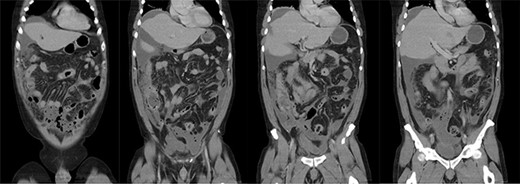

A 51-year-old male presented with 2 days of generalized abdominal pain and profuse watery stools. The pain commenced suddenly and had worsened, becoming so severe the patient was unable to mobilize. The patient’s background medical history consisted only of a supraumbilical hernia repair with mesh 6 years prior, with one colonoscopy 5 years prior completed due to a family history of bowel cancer, which identified a benign polyp. The patient denied any diverticula identified at that colonoscopy. A CT was obtained at presentation that identified a large volume of free gas and free fluid with concern for sigmoid diverticulum perforation (see Figs 1 and 2). At presentation, the patient was haemodynamically stable but had generalized peritonism on abdominal examination. Given the CT and examination findings, an exploratory laparotomy was organized.

Coronal slices of computed tomography scan showing a large volume of free fluid and free gas, with multiple sigmoid diverticula, reported as concerning for perforated sigmoid diverticula.